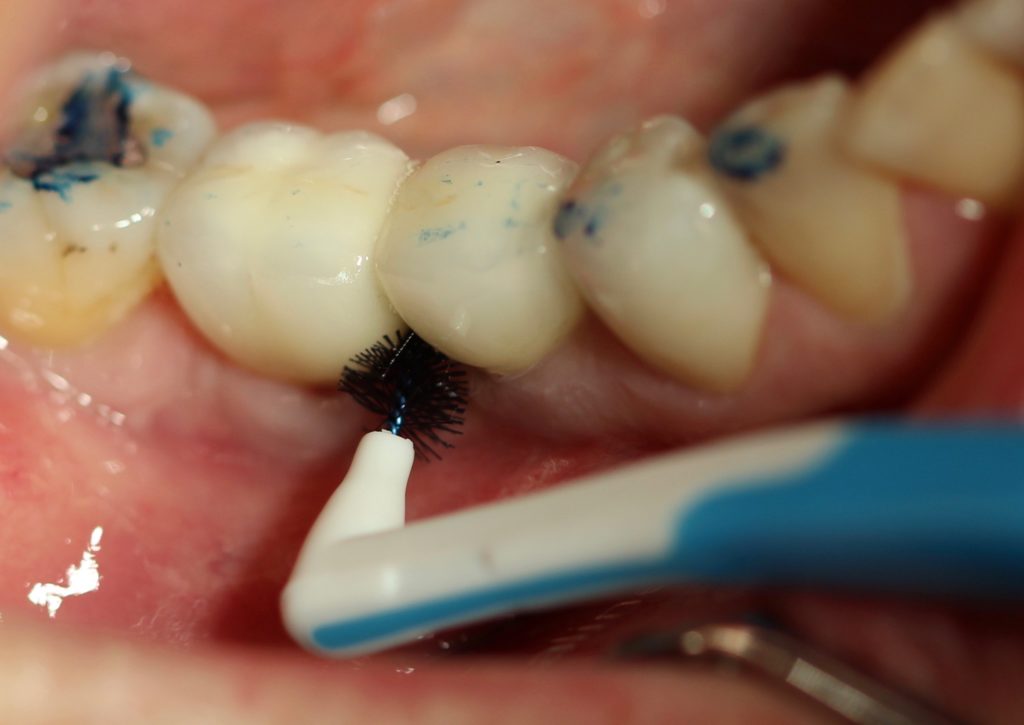

Une séance de maintenance implantaire doit au moins comprendre une révision de l’anamnèse, un examen clinique et radiologique, un entretien motivationnel, un contrôle occlusal et l’élimination des dépôts durs et mous de toute la bouche. L’instrumentation ultrasonique permet un accès dans les poches autour des implants grâce à des inserts spécifiques en titane. Les aéropolisseurs assurent l’élimination des dépôts mous, certaines buses étant utilisées avec des poudres spécialement conçues pour la zone sous-gingivale.

Le patient doit être averti, dès le départ, qu’il est responsable de l’entretien quotidien et qu’il doit respecter un suivi régulier chez son praticien.